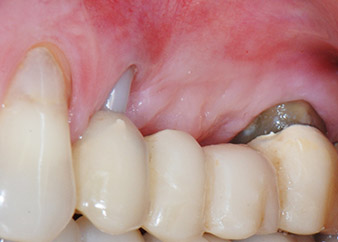

apikale Parodontalläsion an Zahn 24

Abb. 1: Bei einer 58-jährigen Patientin zeigt die Röntgenaufnahme vor der OP eine apikale Parodontalläsion an Zahn 24 und einen horizontalen Knochenabbau im zweiten Quadranten.

Eine 58-jährige Patientin, die auch eine gute Freundin und ärztliche Kollegin ist, beschwerte sich über Schmerzen und erhöhte Beweglichkeit ihres Brückenpfeilers 24. Es lag auch eine parodontale Entzündung vor, mit Taschentiefen von 7 mm mesiobukkal und mehr als 12 mm distal und einer Furkationsbeteiligung dritten Grades. Darüber hinaus zeigte die Röntgenaufnahme eine großflächige apikale Aufhellung am endodontisch (alio loco) vorbehandelten Zahn 24 (Abb. 1).